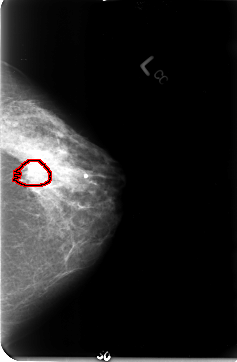

B_3023_1.LEFT_MLO

LEFT_MLO LINES 4648 PIXELS_PER_LINE 3056 BITS_PER_PIXEL 12 RESOLUTION 50 OVERLAY

FILE: B_3023_1.LEFT_MLO.OVERLAY

TOTAL_ABNORMALITIES 1

ABNORMALITY 1

LESION_TYPE MASS SHAPE IRREGULAR MARGINS OBSCURED-ILL_DEFINED

ASSESSMENT 3

SUBTLETY 2

PATHOLOGY MALIGNANT

TOTAL_OUTLINES 1

BOUNDARY